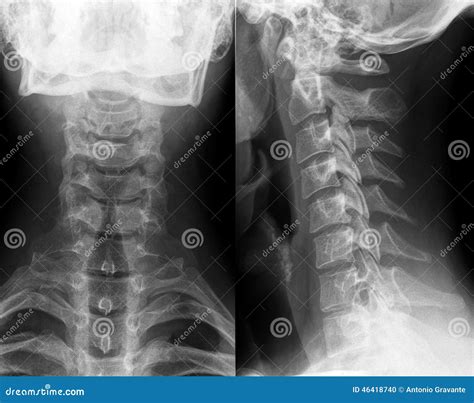

Interpreting a Normal Neck X Ray

Interpreting a Normal Neck X Ray involves examining the images for any abnormalities. Key structures to assess include:

• Vertebrae: The seven cervical vertebrae (C1-C7) should be clearly visible and aligned.

• Intervertebral Discs: The spaces between the vertebrae should be uniform and without narrowing.

• Joints: The facet joints should be well-defined and without signs of degeneration or inflammation.

• Soft Tissues: The soft tissues, including muscles and ligaments, should appear normal without any swelling or masses.

In a Normal Neck X Ray, the following features are typically observed:

Structure Normal Appearance

Vertebrae Well-defined, aligned, and without fractures or deformities.

Intervertebral Discs Uniform spaces between vertebrae, without narrowing or herniation.

Joints Smooth and well-defined, without signs of arthritis or inflammation.

Soft Tissues No swelling, masses, or other abnormalities.